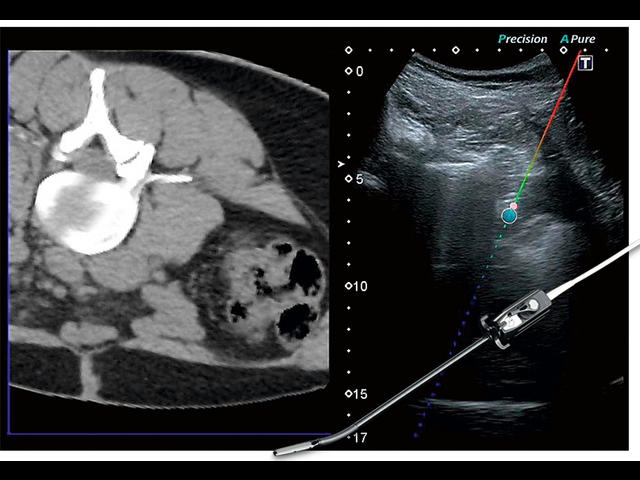

Обновленная версия легендарного УЗ-сканера. Стационарный аппарат экспертного класса Aplio 500 Toshiba NEW, визуализирует анатомические структуры в высоком разрешении. Модель позволяет выявить микрокальцификаты, новообразования, нарушения в работе сердца, сосудов и мышц. Присутствует функция виртуальной эндоскопии, 4D-сканирования, эластометрии тканей, УЗИ с контрастированием. За повышение качества изображения отвечают технологии ApliPure и Superb Microvascular Imaging. Первая задействует возможности пространственного и частотного кодирования, формирует цельный визуальный ряд с сохранением клинических маркеров. Вторая улучшает отображение микрососудистого русла, используя доплеровский эффект. Модель оснащена 21-дюймовым монитором, имеет 4 активных порта. Возможно подключение педиатрических, интраоперационных, лапароскопических и чреспищеводных датчиков.

IFusion:

Да